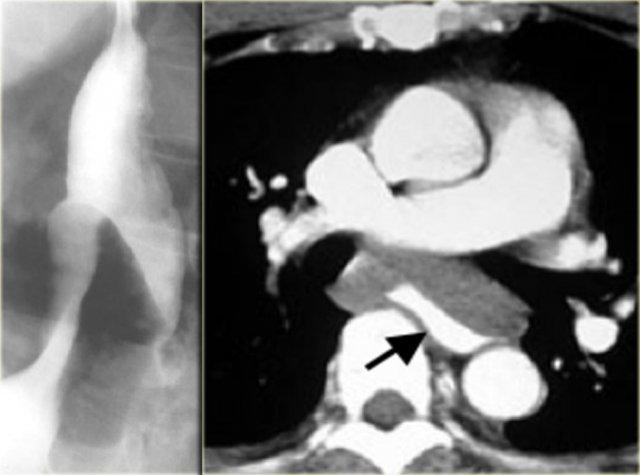

Bên trái là hình ảnh một bệnh nhân mắc hội chứng Boerhaave.

Chụp thực quản barium cho thấy khí ngoài lòng thực quản (mũi tên) mà không có thuốc cản quang thoát ra ngoài.

CT cho thấy khí ngoài lòng thực quản (các mũi tên).

Vết rách ở thực quản đoạn xa bên trái được xác nhận trong phẫu thuật.

CT có thể phát hiện lượng nhỏ khí ngoài lòng thực quản hoặc thoát thuốc cản quang mà không thể nhìn thấy trên X-quang hoặc chụp thực quản cản quang.